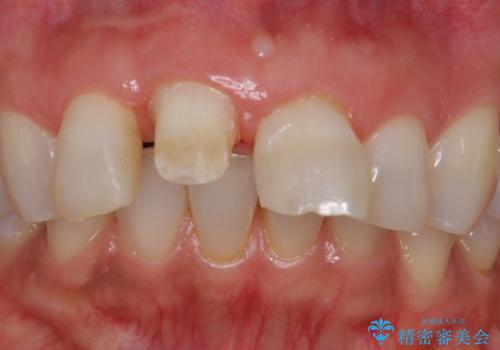

転んで前歯を折った 歯を抜かない治療

- 転んで前歯が折れたとのことで来院されました。

検査の結果、歯は大きく折れておらず、骨の中に埋め込まれていた状態であったため、部分矯正で歯を引っ張り出していきます。